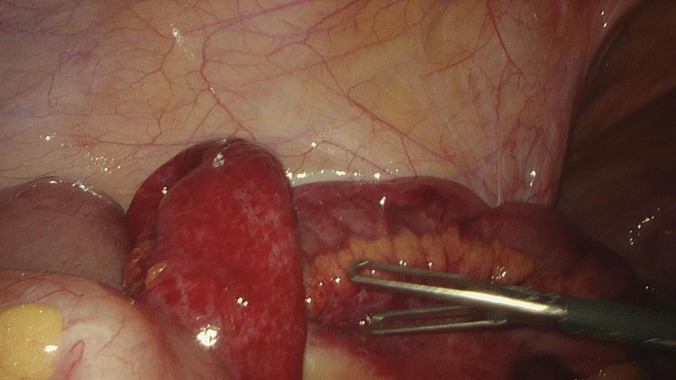

Case description: We treated a 42-year-old female airline cabin crew member who presented with colicky abdominal pain, bilious vomiting, and lower abdominal tenderness. Her abdominal computed tomography (CT) scan showed small bowel obstruction with loops of small bowel predominantly in the left lower abdomen. She had a history of a single episode of similar abdominal pain many years prior, which resolved spontaneously. The rest of her history was unremarkable. She received nonoperative management initially, but due to persistent abdominal pain and vomiting, a diagnostic laparoscopy was done. The diagnostic laparoscopy showed congested but viable small bowel herniating into a peritoneal defect through the lateral part of left broad ligament at the lateral pelvic wall into the retroperitoneum. The hernia was reduced, and the defect was repaired. Postoperatively, she had an uncomplicated recovery.